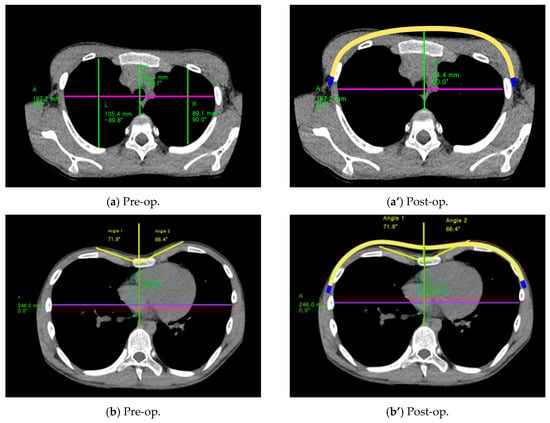

| Point | A (mm): Pre-Op. | A’ (mm): Post-Op. | B (mm): Pre-Op. | C (mm): Post-Op. | HI: Pre-Op. | ICI: Post-Op. |

|---|---|---|---|---|---|---|

| A | 217.86 | 206.97 | 73.01 | 101.11 | 2.98 | 2.05 |

| B | 215.22 | 204.46 | 68.61 | 103.49 | 3.14 | 1.98 |

| C | 217.57 | 206.70 | 73.30 | 104.15 | 2.97 | 1.98 |

| Type | A (mm): Pre-Op. | A’ (mm): Post-Op. | C (mm): Pre-Op. | C’ (mm): Post-Op. | HI: Pre-Op. | ICI: Post-Op. |

| Eccentric (Patient No. 2) | 197.2 | 187.34 | 60.4 | 84.4 | 3.26 | 2.22 |

| Unbalanced (Patient No. 3) | 246.0 | 233.7 | 72.6 | 98.6 | 3.39 | 2.37 |